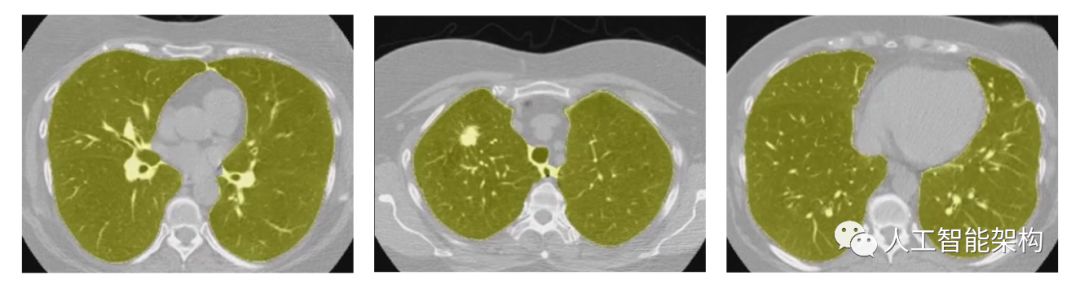

,其中HU值为-1000将映射为0,400将映射为1。最后,对CT图像进行粗略肺部分割,从而消除与肺部不相交区域。

上图为肺部分割例子,其中肺部区域为黄色。